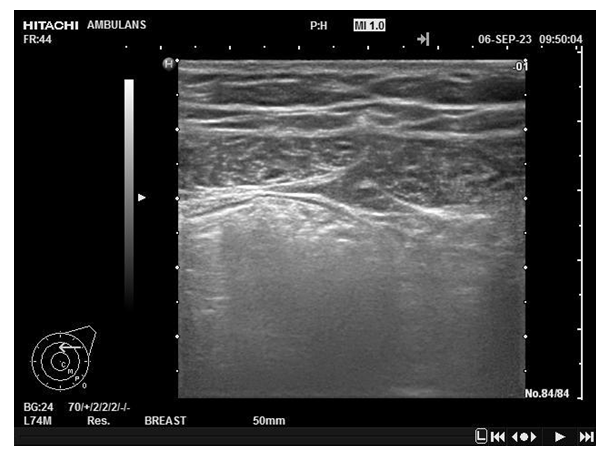

The basis of this study is the analysis of the results of treatment of inguinal hernias using endovideosurgical hernioplasty: TARR, TER and e-TER in 216 patients operated in the Department of Endoscopic Surgery of Samarkand GMO No1 for 8 years (2017-2024).All of them were hospitalized for planned surgical treatment. In accordance with the tasks, the patients were divided into 2 groups. Retrospective groups included 110 patients who underwent the following patients: - TARR hernioplasty – 58 patients; - TER hernioplasty – 52 patients.Prospective groups included 106 patients who underwent the following patients: - TARR hernioplasty – 54 patients; - e-TER hernioplasty – 52 patients.Among the patients, men of middle and older age groups prevailed, which is characteristic of inguinal hernias. All hospitalized patients were diagnosed with primary uni- or bilateral inguinal hernias of I, II or III (A or B) types (according to Nyhus). In the retrospective groups, inguinal hernias were most often found in Type II (oblique with an expanded ring) and Type IIIA (straight). At the same time, among those operated using the TARR techniques, there were more patients with complex types of hernias (Type IIIA and Type IIIB). Bilateral hernias (Type IIIA) were observed in 4 (3.6%) patients, and all of them were operated using the TARR technique.This study involved patients who had previously undergone surgical treatment. In the TARR group, these were 10 (17.2%) patients, and in the TER group – 11 (21.2%). The most common is an open-access appendectomy in the right iliac region.In the prospective groups, inguinal hernias of types II and IIIA were most common in 77 (72.6%) patients.From these, more patients with direct hernias (Type IIIA) were operated using the e-TER technique: 40.4% compared to 33.3% among those, who were operated using the TARR technique. At the same time, the group of patients operated using the TARR technique included 3 (4.6%) patients with concomitant cholelithiasis, chronic calculous cholecystitis, who underwent simultaneous surgical interventions: hernioplasty + cholecystectomy. Patients with type IIIB hernias, which included sliding and inguinal-scrotal hernias, were more often operated on by the e-TER method: 17.3% versus 5.6% in the TARR group. Patients hospitalized with bilateral direct hernias (Type IIIA) were also more likely to be operated on by extended full extraperitoneal hernioplasty (5 (9.6%) patients.Patients with an operative history were much more likely operated using the e-TER technique. Thus, among all patients in whom e-TER was used (n=52), 15 (28.8%) had previously undergone abdominal surgery. In the TARR group (n=54), there were 6 such patients (10.1%), and all previous surgical interventions were performed by endovideosurgery. Ultrasound scanning has found its wide use in instrumental diagnostics of PG. The thickness of the oblique abdominal muscles in patients with PG was significantly less in comparison with healthy individuals. | Figure 1. Criteria for the width of the oblique abdominal muscles (rectus and internal) in patients with inguinal hernia |

| Figure 2. Ultrasound picture of the muscles of the inguinal region in a patient with inguinal hernia |

Muscle thickness indicators during tension in patients with PG changed by 0.192±0.101 cm on average, while in the group of healthy individuals the change in this indicator was more significant – by 1.186±0.109. Consequently, in patients with PH, in contrast to healthy people, a decrease in the width of the oblique abdominal muscles is impaired by muscle tension, which, in fact, is considered a predisposing factor for destructive changes in the tissues of the aponeurosis of the abdominal muscles and an increase in the size of the hernial defect that has arisen.As part of the exclusion of complications (seroma, hematoma) and possible migration of the mesh during the first few days after surgery, all patients underwent ultrasound scanning. Small hematomas and seromas (volume up to 20 ml) were subjected to conservative treatment, large ones (volume more than 20 ml) were punctured under ultrasound control.